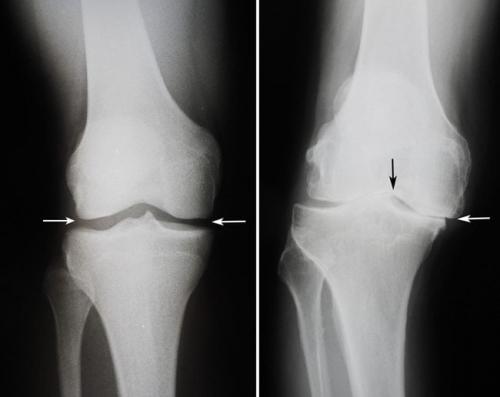

3. Комплексный сустав (art. complexa) , содержащий внутрисуставной хрящ, который разделяет сустав на две камеры (двухкамерный сустав). Деление на камеры происходит или полностью, если внутрисуставной хрящ имеет форму диска (например, в височно-нижнечелюстном суставе), или неполностью, если хрящ приобретает форму полулунного мениска (например, в коленном суставе).

Расположенный между бедром ноги и большой берцовой и малой берцовой костью голени, коленный сустав - самый большой и самый сложный блоковидный сустав в человеческом теле.

- дегенеративно-дистрофические. Чаще встречаются у пожилых людей и лиц, которые постоянно выполняют тяжелую физическую работу. Дегенеративные процессыэто следствие старения организма, которое сопровождается замедлением метаболизма и кровообращения в суставах. Под действием провоцирующих факторов (физические нагрузки, нехватка кальция, обменные нарушения) суставные хрящи начинают разрушаться, что приводит к развитию патологии. Дегенеративно-дистрофические заболевания имеют хроническое, медленно прогрессирующее течение;

- Комплексные суставы (articulatio complex) — имеют суставной диск или мениски (грудино-ключичный, височно-нижнечелюстной, коленный).